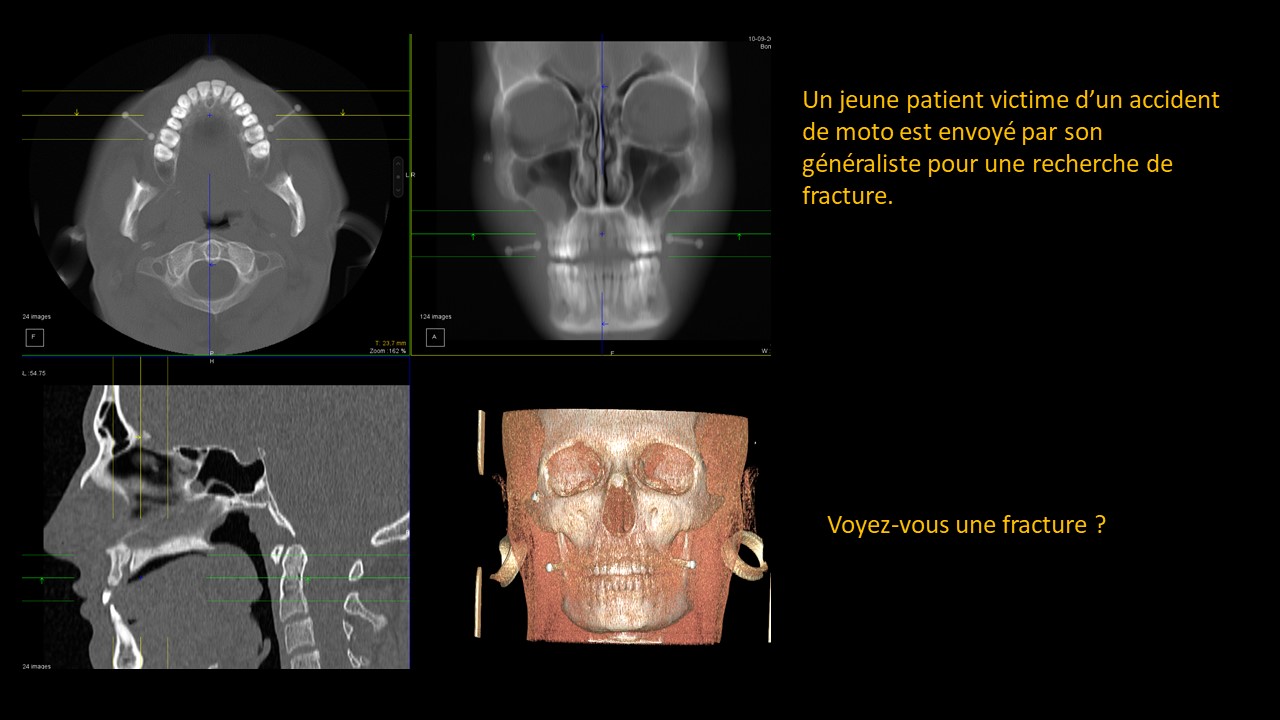

Présentation clinico-radiologique 84

_______ cliquer ici pour la réponse ________